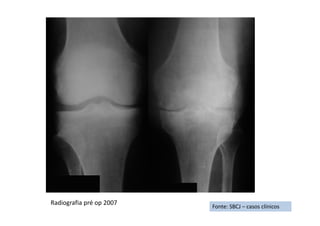

• Solicitados exames radiológicos de ambos os joelhos estes demonstraram a

presença de osteoartropatia degenerativa (artrose) em ambos os joelhos;

Imagem Radiológica da Gonatrose à Esquerda

Esq. Esq.Dir. Dir.